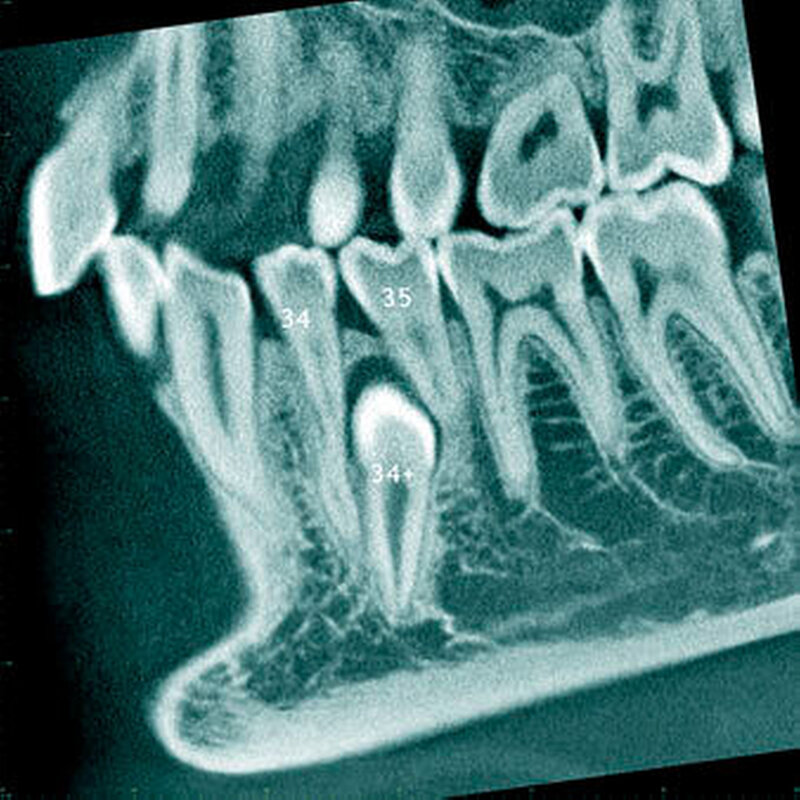

In einer aktuellen Arbeit berichteten Mossaz und Mitarbeiter (2014) über eine relativ hohe Prävalenz (22,8 Prozent) der Wurzel- resorptionen an benachbarten Zähnen, wobei besonders häufig überzählige Prämolaren zu Resorptionen führen (Abbildung 18). Für die Beurteilung der Wurzelresorptionen wurden digitale Volumentomografie (DVT) der Patienten herangezogen. In einer Studie aus China, welche ebenfalls DVT-Bilder beurteilte, wurde über eine deutlich geringere Häufigkeit von Wurzelresorptionen (1,6 Prozent) berichtet [Liu et al., 2007]. Im Gegensatz zu den Daten aus der Schweiz war Diagnose und Bewertung von Wurzelresorptionen kein primäres Ziel dieser Studie und es wurde auch keine Information über das Ausmaß der Resorptionen gegeben.

Daher könnte diese Studie leichte oder mäßige Wurzelresorptionen nicht eingeschlossen haben, was zumindest einen Teil des doch deutlichen Unterschieds in den Prozentsätzen erklären würde. Studien, welche Panoramaschichtaufnahmen zur Diagnose von Wurzelresorptionen heranziehen, berichten über Resorptionsraten zwischen 4,7 Prozent [Gündüz et al., 2008] und 7,6 Prozent [Hyun et al., 2009]. Tyrologou und Mitarbeiter (2005) berichteten sogar, dass keine Resorption im untersuchten Patientengut vorhanden waren. Allerdings wurden in dieser Studien nur Mesiodentes beurteilt, wo Wurzelresorption benachbarter Zähne eher selten vorkommen [Mossaz et al., 2014]. Generell lässt sich festhalten, dass zweidimensionale Röntgenaufnahmen für die Diagnose von Wurzelresorptionen eher ungenau sind und diese so in bis zu 50 Prozent der Fälle übersehen werden [Ericson Kurol, 1987, Heimisdottir et al., 2005; Botticelli et al., 2011; Alqerban et al., 2011a].